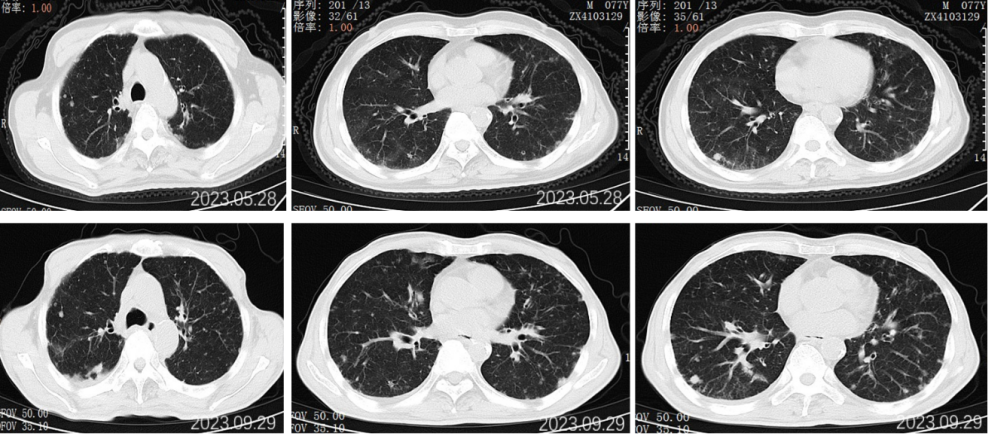

2022.07.20胸部CT示:两肺多发小结节,考虑转移;两侧胸腔少量胸腔积液。头颅MR、骨ECT未见明显异常。

2022.09.27胸部CT平扫:1.两肺多发小结节、类结节影,较前相似,转移性考虑;2.两侧胸腔少量积液较前已吸收。3.左侧第5后肋骨质破坏。

2022.11.25胸部CT平扫:对比2022-09-27影像:1.新见两肺多发间质性肺炎样改变,感染考虑,VP-RADS 2类;2.两肺多发小结节、类结节影,部分较前略缩小,转移性考虑;3.左侧第5后肋骨质破坏,相仿。

2023.5.28胸部CT平扫:对比2022-11-25片:1.两肺散在多发炎症,较前相仿,VP-RADS 2类;2.两肺多发小结节、类结节影,转移瘤考虑,较前相仿;3.左侧第5后肋骨质异常,相仿。男性乳腺发育。

2023.09.29胸部CT平扫:对比2023-05-28片:1.两肺多发小结节、类结节影,较前增多增大,转移瘤考虑。2.两肺散在多发炎症,部分较前吸收;3.左侧第5后肋骨质异常,相仿;4.右侧胸腔少量积液。男性乳腺发育。